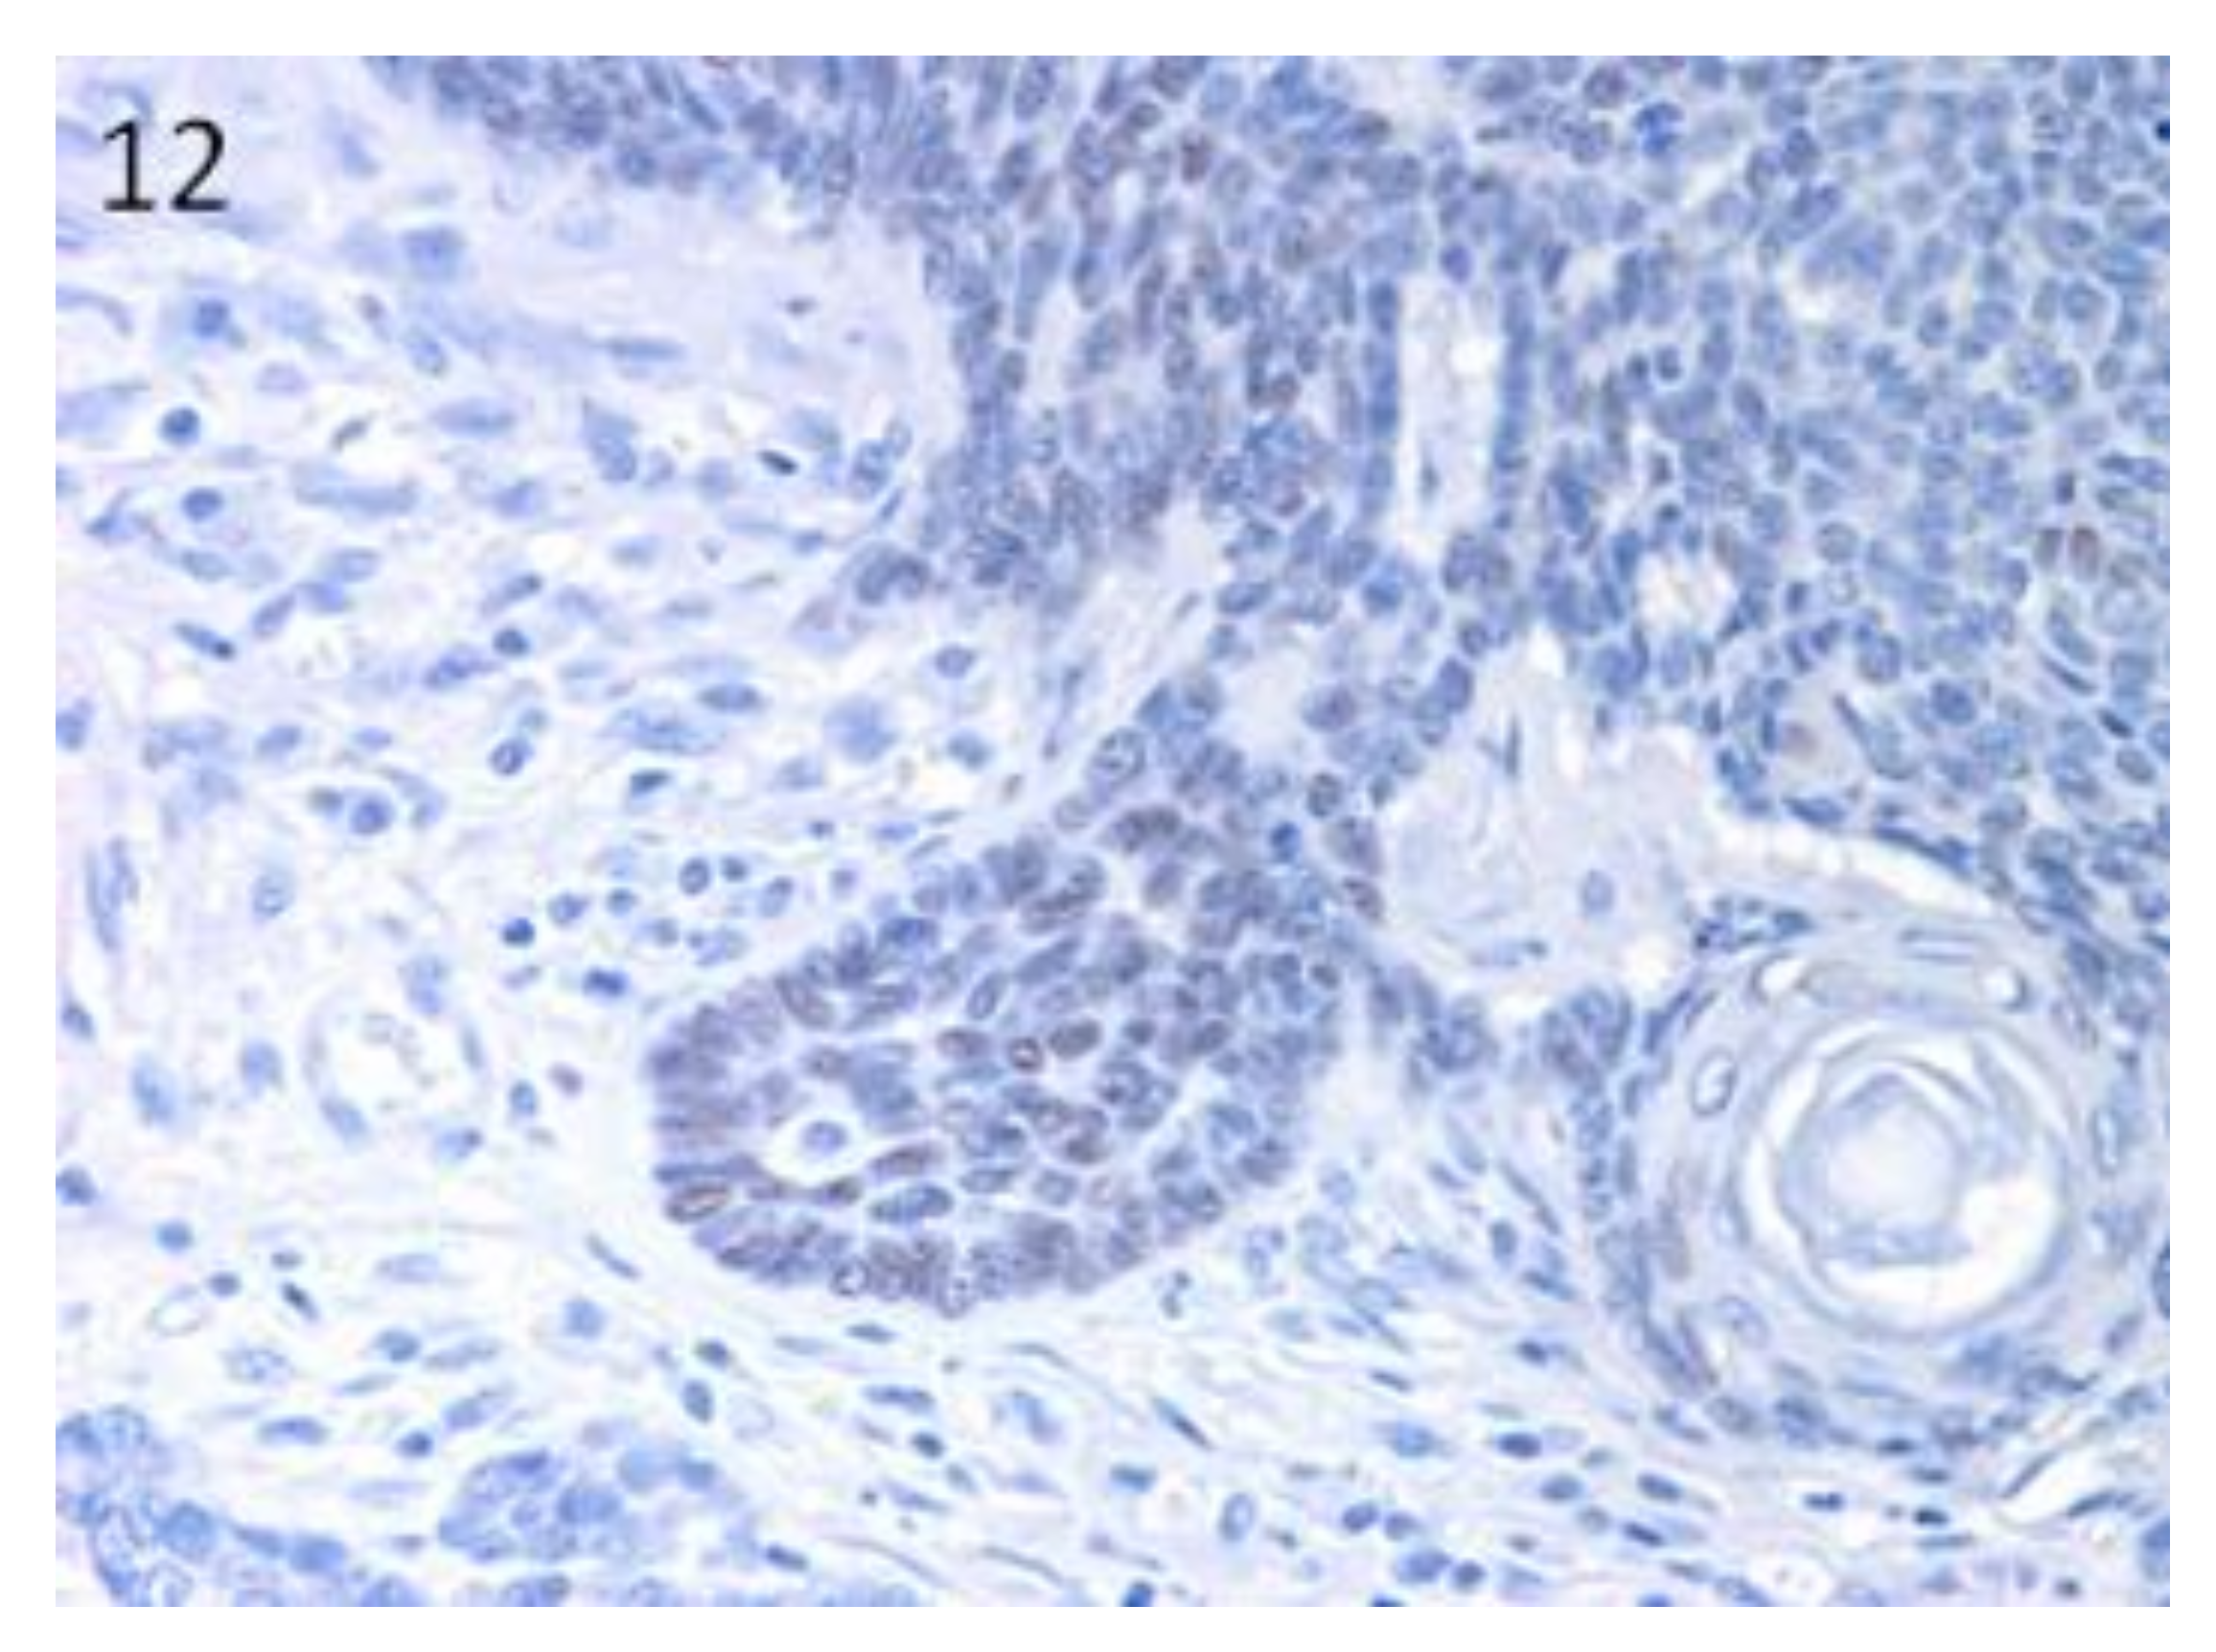

Sox9-positive cells were mainly present among the basaloid neoplastic cells of infundibular keratinizing acanthoma (Figure 8). The immunolabelling was evident in the inner parts of the nests of the TB, in both ribbon (Figure 9) and trabecular types, while only scattered positive nuclei were evident in the TL samples (Figure 10). In the PM cases, neoplastic cells with matrical cell morphology were negative; however, single or small clusters of positive cells were evident among these negative matrical cells (Figure 11). A heterogeneous expression pattern based on the predominant hair follicle differentiation was observed in TE samples (Figure 12), with no difference between the benign and malignant forms.

Figure 12.

TE: groups of positive neoplastic cells within the parts of the tumour with basal cell morphology. Negative cells with squamous differentiation. Magnification 40×.